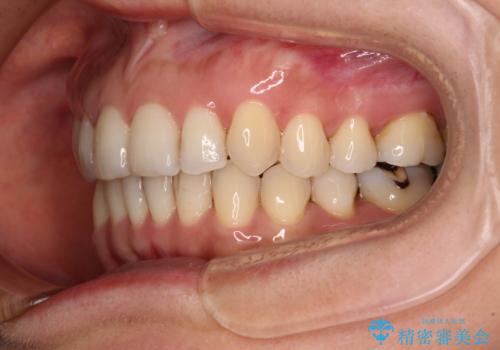

- 矯正治療の後戻りを気にして来院された患者様です。

後戻りは軽微であったので、インビザライン・ライトにより矯正治療を行うこととしました。